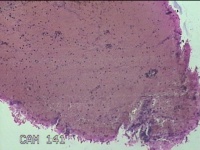

子宫颈管组织

性别

女

年龄

46岁

子宫腺肌症 子宫内膜增生 子宫内膜息肉?原发性不孕症

一般病史

月经不规则伴月经量多3年。

标本名称

大体所见

灰白暗红色不规则碎组织2x1.3x0.7cm一堆。